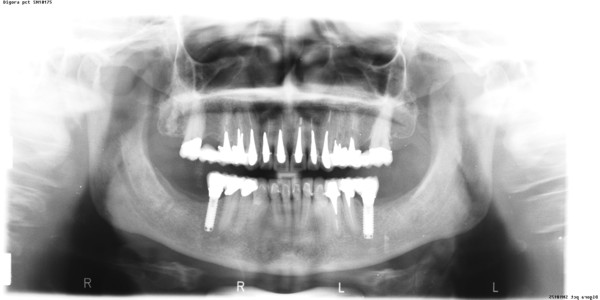

APRECIACIONES DIAGNÓSTICAS EN BASE A LA APERTURA MENTAL DEL CLÍNICO FRENTE A LO QUE EL PACIENTE PROPONE EN MUCHAS OCASIONES , LA DEMANDA DE LOS PACIENTES NOS INCLINAN A FOCALIZAR NUESTRA ATENCIÓN EN LAS PIEZAS DE LAS CUALES EL ENFERMO SE QUEJA. PACIENTE SEXO FEMENINO, 55 AÑOS, SE PRESENTA A LA CONSULTA DERIVADA POR COMPAÑERO GENERALISTA, QUIEN LLEVA MESES PROCEDIENDO A LA «DESINFECCIÓN» DE UN PRIMER PREMOLAR IZQUIERDO, EL QUE SE PRESENTA ABIERTO EN SU CONDUCTO EN EL AFÁN DE PERMITIR EL ESCAPE DE GASES DE UNA GANGRENA PULPAR. A LA INSPECCIÓN CLÍNICA SE OBSERVAN FACETAS PARAFUNCIONALES DE TERCER GRADO , ASINTOMÁTICAS, CON EVIDENTES DIFICULTADES MASTICATORIAS Y ESTÉTICAS , FALTA TOTAL DE SUS MOLARES INFERIORES, Y ADELANTAMIENTO PRONUNCIADO DE SU MANDIBULA, LA QUE CUESTA MANIPULAR DEBIDO A LA SITUACIÓN DE ESPASMO DE CASI TODA SU MUSCULATURA GNATICA. SE ESTUDIA EL CASO RADIOLOGICAMENTE, Y SE RELAJA EL SISTEMA MEDIANTE LAM. DE LONG REALIZANDO UN MONTAJE EN LA ORC OBTENIDA. NO SATISFECHOS CON EL RESULTADO, CONFECCIONAMOS UN JIG DE LUCIA, EL QUE DEJAMOS EN BOCA TODA UNA NOCHE, AL CABO DE LA CUAL REALIZAMOS UN NUEVO REGISTRO REALIZAMOS UN ENCERADO RÁPIDO DEL CASO, Y CONFECCIONAMOS UNA ESTRUCTURA OCLUSAL PLASTICA, QUE ADEMÁS REPONGA EL ASPECTO ESTÉTICO PERDIDO (FÉRULA DE RELAJACIÓN DE COMPONENTE ESTÉTICO), LO QUE PERMITE AL ENFERMO LUEGO DE DOS DÍAS DE USO, NO SOLO CORROBORAR LA COMODIDAD MASTICATORIA Y LA FALTA DE SÍNTOMAS MUSCULARES, SINO TAMBIÉN OBSERVAR APROXIMADAMENTE LA DIFERENCIA ENTRE LA SITUACIÓN INICIAL Y LO QUE PUEDE LOGRARSE MEDIANTE EL TRATAMIENTO. EL PACIENTE ADVIERTE LA MEJORÍA DE LA SITUACIÓN. ACEPTADO POR PARTE DEL MISMO EL TRATAMIENTO SUGERIDO, CREAMOS UN JUEGO COMPLETO DE PROVISORIOS EN BASE AL ENCERADO, Y PROCEDEMOS A TRATAR LA INFRAESTRUCTURA, QUE CONSISTE EN LAS ENDODONCIAS, SUS REFUERZOS A PERNOS DE ORO, LOS ASPECTOS PERIODONTALES DEL CASO, Y DOS IMPLANTES INFERIORES CON TÉCNICA SEMISUMERGIDA ,DE 5 MM DE ANCHO POR 12 DE LONGITUD, CON ANILLO DE ZIRCONIO , A LA ESPERA DE OSTEOINTEGRACIÓN, TRANSCURREN TRES MESES EN EL USO DE UNA NUEVA OCLUSIÓN CONSTITUIDA POR LOS PROVISIONALES, SEGÚN EL ENCERADO, QUE SE REALIZÓ SIGUIENDO LOS CÁNONES DE UNA OCLUSIÓN ORGÁNICA. COMPROBADA LA EFICACIA DE LA NUEVA SITUACIÓN, CON SUS DISCLUSIONES LATERALES Y POSTERO ANTERIORES CORRECTAS, CARECIENDO YA DE SINTOMATOLOGÍA MUSCULAR (SIN MIALGIAS, SIN MIOSITIS, Y CON UN GRADO DE APERTURA DE 4,50 CM), Y SIN SIGNOS EVIDENTES DE DESGASTE SOBRE EL MATERIAL DE LOS PROVISORIOS, ES DECIR: VERIFICANDO QUE EL PACIENTE YA NO BRUXA, VERTICALIZANDO EL CICLO MASTICATORIO /OTORGANDO ORC/ DIMENSIÓN VERTICAL /PROTEGIENDO A LAS PIEZAS `POSTERIORES DE IMPACTOS LATERALES RECIEN ENTONCES , MONTAMOS EN ARTICULADOR SEMI AJUSTABLE LOS MODELOS DE TRABAJO DEFINITIVOS. CONFECCIONAMOS ENTONCES LAS COFIAS INFRA PORCELANA, EN PORCELANA DE ALTA DENSIDAD EN EL SECTOR ANTERIOR Y EN ORO GALVÁNICO PARA EL SECTOR POSTERIOR PARA LUEGO COMPLETAR LA GUIA ANTERIOR , VERIFICANDO LA ALTURA DE LOS INFERIORES RESPECTO DEL LABIO INFERIOR Y CORROBORANDO LOS PUNTOS DE CONTACTOS INTER CANINOS, QUE CENTRALIZAN LA MANDIBULA Y VERTICALIZAN EL CICLO MASTICATORIO Y LAS DISCLUSIONES CANINAS QUE OTORGARÁN PROTECCIÓN A LOS SECTORES POSTERIORES. POSTERIORMENTE CHEQUEAMOS LA DISCLUSIÓN EN PROPULSIVA DE LA GUIA ANTERIOR YA TERMINADA. FIG38 FIG39 UNA VEZ OBTENIDO UN COMANDO ANTERIOR EFECTIVO, COMO LO ES LA GUIA ANTERIOR CON TODOS SUS COMPONENTES, PROCEDEMOS A REALIZAR LAS TABLAS PREMOLAR / MOLAR DE AMBOS LADOS Y OBSERVAMOS QUE LOS PUNTOS INTEROCLUSALES DE CONTACTO SEAN SUFICIENTES Y CUMPLAN SU OBJETIVO DE OTORGAR ESTABILIDAD MESIO DISTAL Y VESTÍBULO LINGUAL. TRANSCURRIDO UN AÑO DE FINALIZADO EL TRATAMIENTO, REALIZAMOS UN CHEQUEO POST OPERATORIO DEL CASO, EN TODOS LOS PARÁMETROS ANTERIORMENTE MENCIONADOS, Y OBSERVAMOS LA ABSOLUTA ESTABILIDAD DEL MISMO EN TODOS SUS NIVELES Y TEJIDOS.